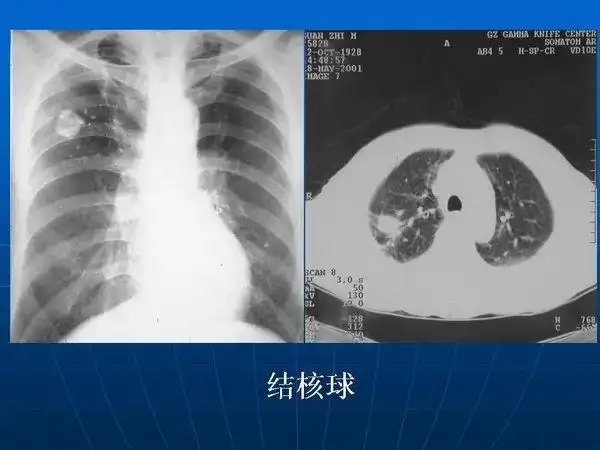

各型肺结核的典型影像表现

肺结核ct影像表现

肺结核及其肺部ct影像特征